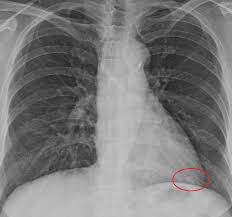

- 흉부 X‑선 또는 흉부 CT로 발견

- 결절 크기·형태·경계·석회화 여부 등 특징 분석